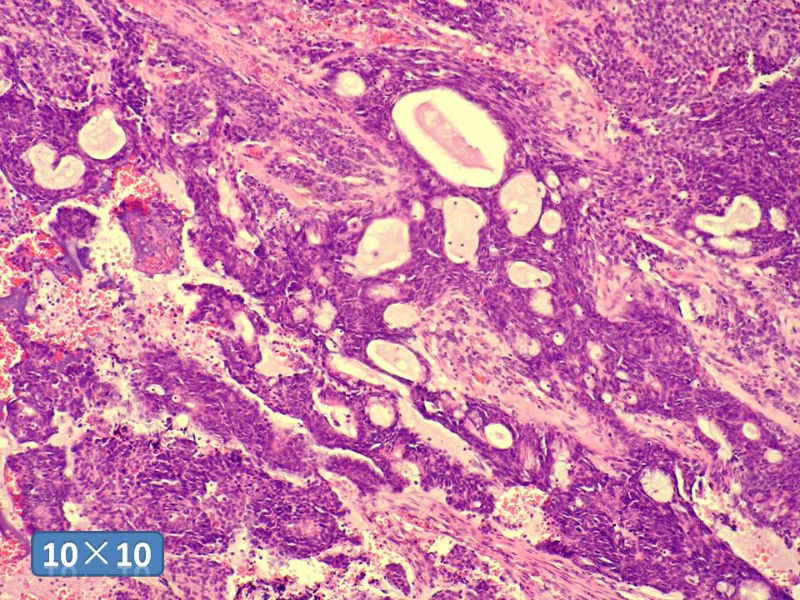

男性,49岁,间断左鼻腔出血3个月。

标签:是嗅母么?

1)嗅神经母细胞瘤?

2)腺肌上皮癌?

3)肌上皮癌?

4)神经内分泌癌?

5)腺样囊性癌?

6)其他?

腺肌上皮癌

感觉要排除畸胎癌肉瘤。

间质为恶性梭形细胞成分,其间感觉是腺体,两种成分密切相关....

免疫组化S-100的阳性区域方式...嗅母可能性大。

支持嗅神经母细胞瘤(伴有腺体分化)